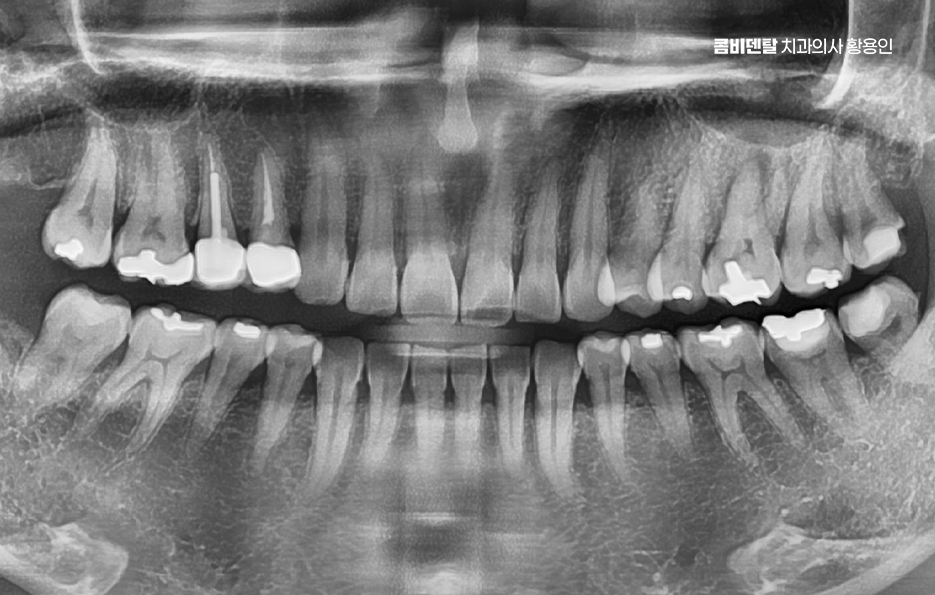

출처 아카이브 열기처음 인레이 치료를 받았을 땐, 사실 그렇게까지 큰일로 받아들이진 않았어요. 치아에 충치가 조금 생겼고, 그걸 레진으로 떼우기에는 깊이가 있고 강도도 걱정된다고 해서 인레이 치료를 권유받았어요 실제로 치료 이후엔 전혀 불편함이 없었어요. 음식을 씹을 때도, 양치를 할 때도, 입 안에 이물감이 없다 보니 마치 원래부터 그 상태였던 것처럼 느껴졌고, 인레이를 했다는 사실조차 자주 잊고 살았어요. 특히 충치 때문에 겪었던 찌릿한 통증이 완전히 사라졌고, 이제는 완전히 문제가 해결되었다는 안도감이 오히려 방심을 불러왔던 것 같아요. 그러다 시간이 조금씩 흘렀어요. 1년, 2년, 그렇게 몇 해가 지나면서도 딱히 문제는 없었어요. 워낙 바쁜 일상에 치과 검진은 늘 뒷전이었고, 양치는 하루 두 번이면 충분하다고 생각했고, 커피를 하루 세 잔 마셔도, 견과류를 매일 씹어도, 나름 치아 건강엔 자신이 있었어요. 그렇게 습관처럼, 인레이 치료 이후의 관리도 습관처럼 대충 넘기면서 살아왔는데, 언제부턴가 이상한 느낌이 시작됐어요. 처음엔 음식물이 잘 껴서 불편하다는 정도였어요. 인레이가 들어간 그 어금니 쪽에 자꾸 음식물이 끼고, 양치 후에도 뭔가 남아있는 것 같은 찝찝함이 있었는데, 그러려니 하고 치실로 해결했어요. 그런데 어느 날은 뭔가를 씹는 순간, 딱딱한 게 이 사이에서 순간적으로 미끄러지는 느낌이 들었고, 그 뒤로는 그 치아에 약간의 통증이 찾아왔어요. 처음엔 무시했어요. 치아가 민감해졌나 보다, 며칠 지나면 괜찮아지겠지 하면서 대수롭지 않게 여겼고, 진통제를 한두 번 먹으면 어느 정도 괜찮아졌기 때문에 또 방심하게 됐어요. 하지만 그 시기가 지나면서부터 상황은 급격히 나빠졌어요. 통증은 더 자주, 더 깊이 왔고, 뜨거운 국물을 마실 때나 차가운 음료를 마실 때, 유난히 그 치아 하나가 반응을 하더라고요. 특히 씹을 때 그 치아에 미세한 통증과 묘한 압력이 느껴지는데, 그게 그냥 아프다는 차원이 아니라 안에서 무언가 망가지고 있다는 감각이었어요

이처럼 많은 분들이 과거에 보철 치료를 받은 후에 시간이 지나면서 치료를 받았었다는 사실 조차 잊고 살아가는 경우가 많지만 보철물은 수명이 존재하며 잘 관리해야만 수명 유지도 가능하기 때문에 어느날 과거에 잊고 지냈던 보철 치료를 받았던 치아가 문제 생겨서 더 큰 치료를 받게 되는 경우가 있는데요

인레이 치료는 충치가 어느 정도 깊이 진행됐을 때 치아 형태를 유지하면서 기능을 회복하는 데 좋은 선택으로서 레진보다 강도는 높고, 크라운보다는 치아 삭제량이 적어서 중간 단계 치료로 자주 사용되는 방식이기도 한데 인레이 치료가 한 번 끝났다고 해서 그 치아가 완벽하게 안전해진 건 아니며 관리가 잘 안 되거나, 본인에게 맞지 않는 사용 습관이 반복되면 인레이를 했던 치아가 다시 충치가 생기거나, 보철물 혹은 주변 치아가 깨지면서 결국 신경치료까지 가는 경우도 있었어요

인레이 치료 후 신경치료 까지 가는 대표적인 케이스 중 하나는 2차 충치, 그러니까 인레이와 치아 사이에 다시 충치가 생기는 경우로서 인레이는 금이나 세라믹 같은 재료로 제작되는데 아무리 정밀하게 맞췄다 해도 그 접합부는 시간이 지나면서 아주 미세한 틈이 생길 수 있어요.

거기에 음식물이나 세균이 침투하게 되면 눈에 보이지 않는 사이에 충치가 다시 시작되는 것이며 특히 칫솔질만으로는 인레이 경계 부분을 완전히 관리하기 어렵고 치실이나 치간칫솔 사용이 소홀한 분들에게 이런 2차 충치가 더 자주 생길 수 있었어요

두 번째로는 보철물 자체가 파절되는 케이스로 인레이는 치아 만큼이나 강하지만 부서지지 않는 건 아닌데 특히 딱딱한 음식이나 얼음, 오징어 같은 질긴 걸 자주 씹는 습관이 있는 경우, 반복적인 교합 압력 때문에 인레이가 금이 가거나 쪼개지는 일이 생길 수 있으며 이때 보철물이 살짝 금 간 정도면 다시 본을 떠서 인레이를 교체하면 되는데 문제는 인레이가 파절되면서 그 안에 있는 치아 조직까지 손상시키는 경우로 치아는 한 번 금이 가기 시작하면 내부까지 확산되기 쉬워서, 그 틈을 따라 세균이 침입하고 결국 치수염, 즉 신경에 염증이 생기게 되는 거예요.

인레이 치료 후 신경치료 케이스 다음으로는 인레이 아래쪽 치아 균열이나 미세 파절이 이미 진행 중이었는데 발견이 늦어진 경우로 이런 경우는 환자 본인이 특별히 통증을 느끼지 않는 한 알기 어렵고, 인레이 치료 후 한동안 잘 쓰다가 갑자기 시큰거리거나 찬물에 민감해지면서 이상을 느끼게 되는데 엑스레이로도 미세 균열은 바로 확인이 어렵기 때문에 증상이 나와야 겨우 파악되며 이때는 신경까지 손상이 된 경우가 많아서 결국 신경치료를 해야 하는 상황으로 연결되는 경우도 있었어요